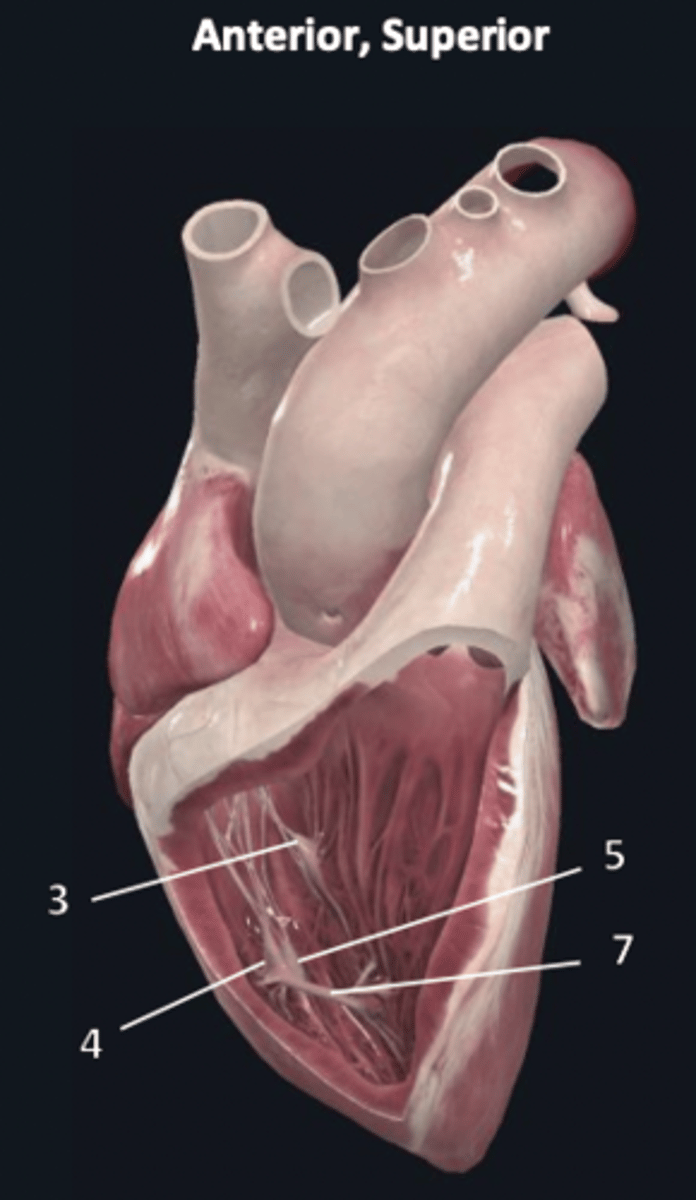

septal papillary muscle

3

anterior papillary muscle

4

inferior papillary muscle

5

chordae tendineae

6

moderator band

7

tricuspid valve

8

pulmonary semilunar valve

9

interventricular septum

10